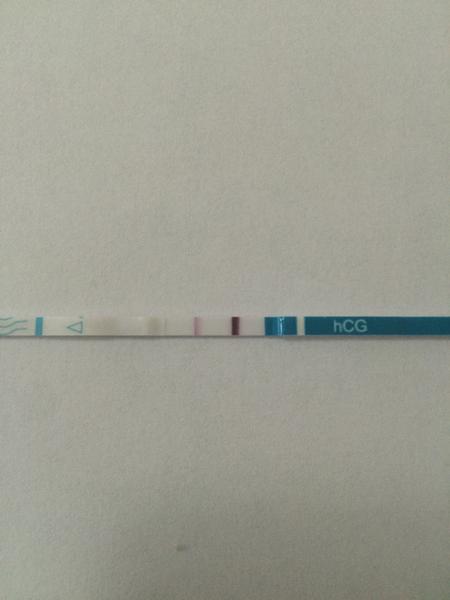

Q: Ktoré tehotenské testy sú najcitlivejšie a ktoré ukazujú odhad týždňov?

A: Najcitlivejšie sú testy označené ako „10 mIU“; digitálne testy ako Clearblue digital sú odporúčané pre ľahké čítanie a niektoré digitálne modely zobrazujú odhad týždňov tehotenstva (v diskusii spomínané až do 3+ týždňov); orientačná cena Clearblue digital v diskusii bola cca 200 Kč a niektoré testy v zahraničí stáli aj 20 €.

@mimikas mojkaaaa testik je naaaadhernyyyy 😵 Vsetko je v poraaaadecku :-*

@sara34valentina no uz to beriem tak viac v pohode, pevne verim ze bude vsetko ok, dnes y testik bol uz krasny, verim ze je vsetko ok a budem sa tesit z miminka

@sara34valentina danav test dneska som urobila